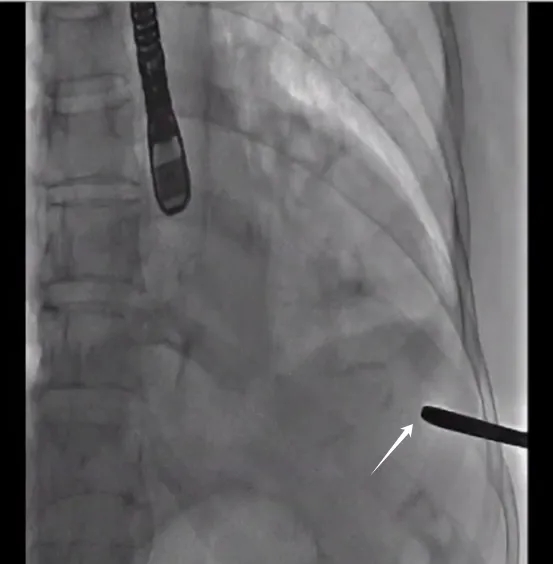

➤导丝跨瓣建立瓣膜植入轨道

▲经股动脉鞘送入“猪尾”导管至主动脉根部

▲导丝进入升主动脉

▲导丝紧贴室间隔

跨过主动脉瓣口

▲沿导管将导丝

送入髂动脉平面

▲主动脉根部造影

手术操作要点:

经心尖荷包正中送入穿刺针,针尖垂直于心肌刺入。心室收缩能见鲜红的氧合血喷出可以初步确定进入左室。当确定有鲜红血液喷出时,保留穿刺鞘退出穿刺针,送入导丝尝试跨过主动脉瓣口,过瓣后用TEE确认导丝是否缠绕二尖瓣腱索。若在超声下看到导丝紧贴室间隔进入升主动脉,说明没有缠绕腱索;若看到导丝是靠二尖瓣前瓣侧进入升主动脉,大概率缠绕了腱索。如果存在缠绕,应撤出导丝,避开缠绕后重新跨瓣。

DSA下沿导管将导丝送入髂动脉平面,可避免后续操作过程中导丝进入腹腔重要分支血管导致损伤,经加硬导丝交换成16F 鞘管,一方面可扩张穿刺点以利于植入器顺利进入,另一方面可以装载球囊用于预扩和后扩。单纯AR患者绝大多数情况下无需球囊预扩。